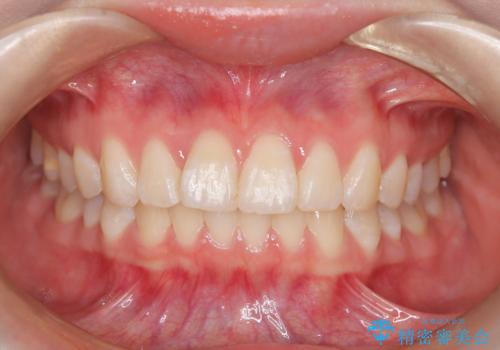

目立たない装置でデコボコを改善 ハーフリンガルによる矯正治療